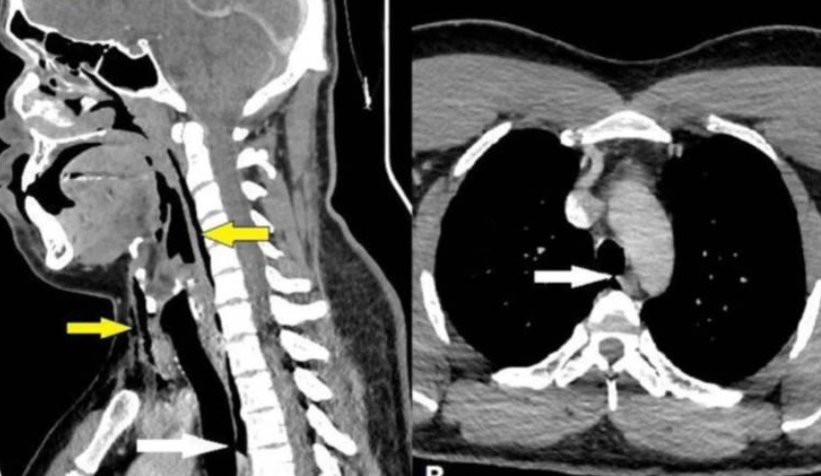

Röntgen çekildikten sonra, "cerrahi amfizem" adı verilen ve havanın kişinin vücudundaki en derin dokunun altında sıkışıp kalabildiği bir rahatsızlığı olduğu anlaşıldı. Hava, adamın boynundaki omurların yanı sıra göğsü ile akciğerleri arasındaki boşlukta sıkışıp kalmıştı.

Doktorlar tarafından yapılan kontroller neticesinde adamın ameliyata ihtiyacı olmadığı ve yırtığın, "soluk borusunda oluşan basınçtan kaynaklandığı" belirlendi.